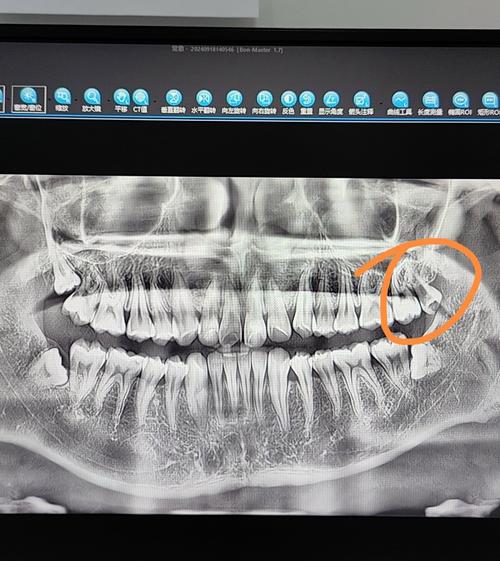

- 术前检查:通过口腔全景片(曲面断层片)或CBCT(锥形束CT)判断智齿位置、萌出方向、与邻牙及下牙槽神经的关系,评估手术难度,若存在急性炎症,需先抗炎治疗,待炎症控制后再拔除。